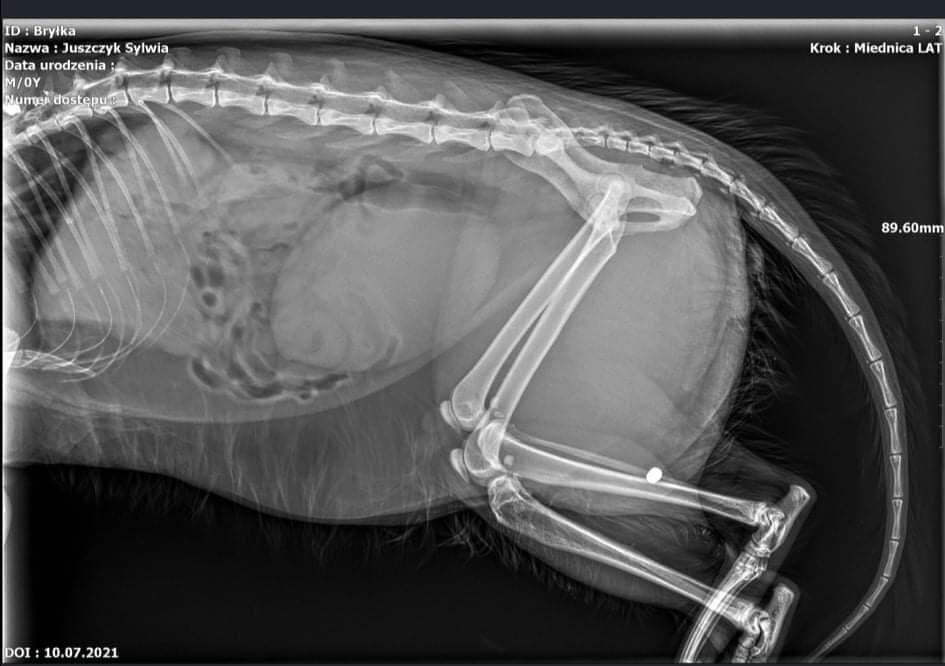

– Niestety nie wiadomo, gdzie doszło do zdarzenia i kto jest jego sprawcą. Pewne jest jednak to, że u zwierzęcia badanie rentgenowskie wykazało obecność śrutu, który prawdopodobnie doprowadził do dysfunkcji rdzenia kręgowego zwierzęcia – przekazuje asp.szt. mgr Kamila Siedlarz, oficer prasowy Komendy Miejskiej Policji w Żorach.

– Wygląda na to, że śrut uszkodził albo uciska rdzeń. Bo jeden ze śrutów i jego części utkwiły w okolicach kręgosłupa. W tej chwili Bryłek otrzymuje leki i lekarze zastanawiają się czy konieczna będzie operacja.W czwartek zostanie podjęta decyzja, czy konieczny będzie tomograf – opisują stan zdrowia Bryłka członkowie fundacji Pet Patrol.– Zrobimy wszystko, aby Bryłek wrócił do zdrowia, a Pani Teresce nie pękło serce – dodają.